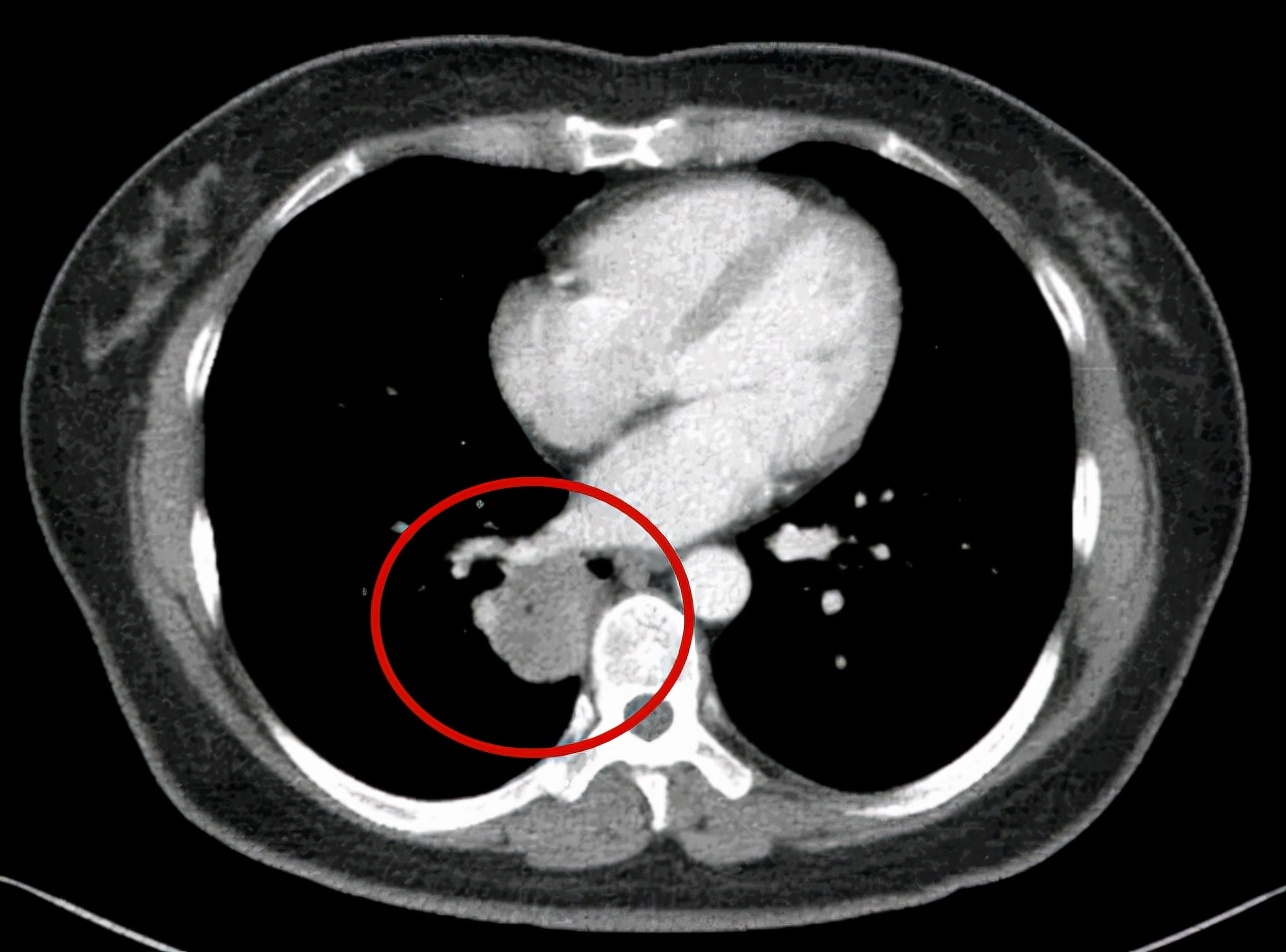

上图示纵隔窗

问诊建议:右下叶红色圈起来的考虑是肺癌,浸润性腺癌可能性大;右上叶磨玻璃结节粉色圈起来的考虑原位癌或不典型增生可能性大,不能完全除外微浸润性腺癌;绿色圈起来的基本上是叶裂处,从密度来看更像良性,但因为有右下叶的病灶在,且在叶间部位,也可能是种植转移,但术前较难确定。PET-CT可以考虑,但也有假阴性或假阳性。我的想法是如果没有远处其他确切转移,建议胸腔镜下探查,如果微小实性结节非转移性,则右下肺癌仍能手术的。如果真若是转移,也可取行病理依据,并送基因检测与免疫组化等检查,而单孔胸腔镜下探查下创伤小,恢复快,当然若不是转移,顺便镜下行右下叶切除并清扫淋巴结就行。